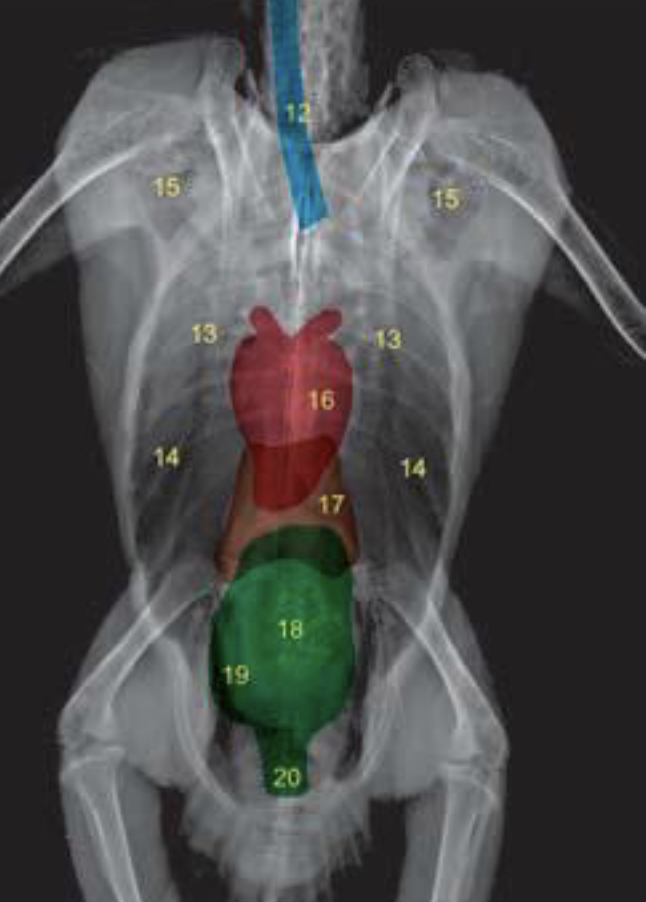

What are the anatomical structures labelled in this image?

A

19: intestines

17: liver

14: thoracic and abdominal air sacs

16: heart

15: diverticula; clavicular air sacs

20: cloaca

13: lung

18: ventriculus